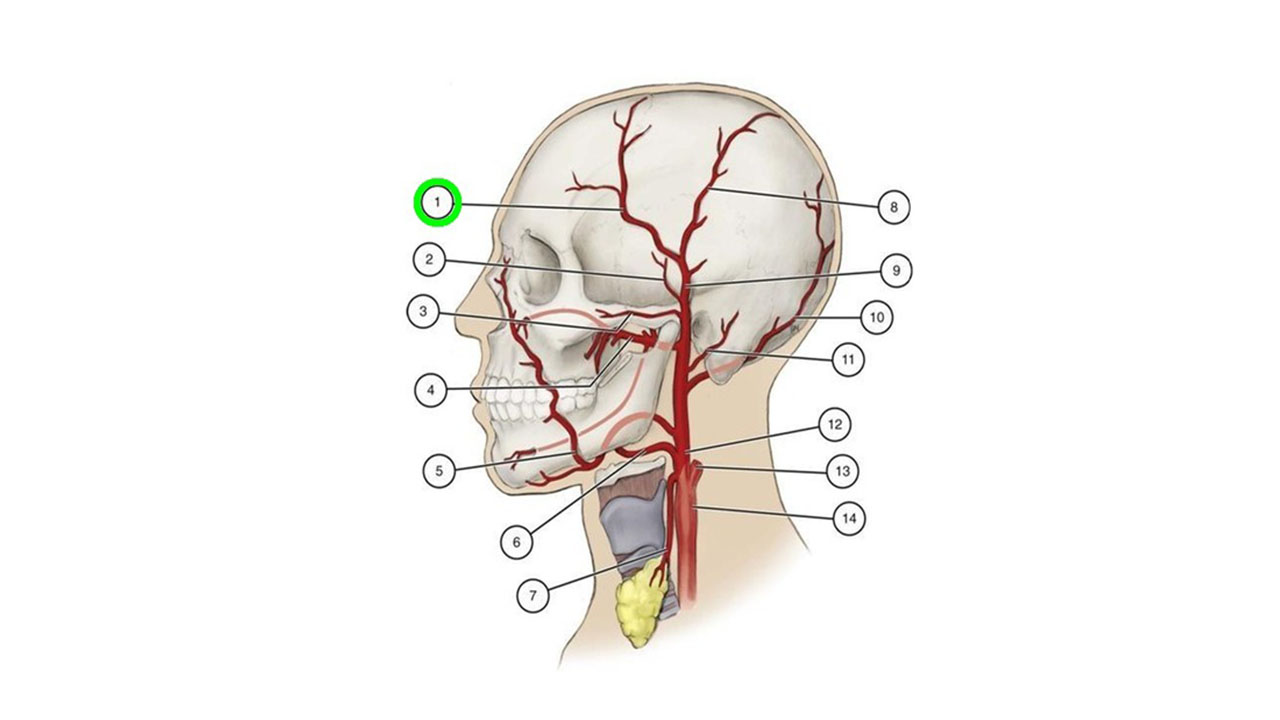

"Limb Doppler (Arterial/Venous): Precise Vascular Assessment for Your Limb Health. AYUSH ULTRASOUND & DIAGNOSTICS - Your Vascular Well-being, Our Expertise."